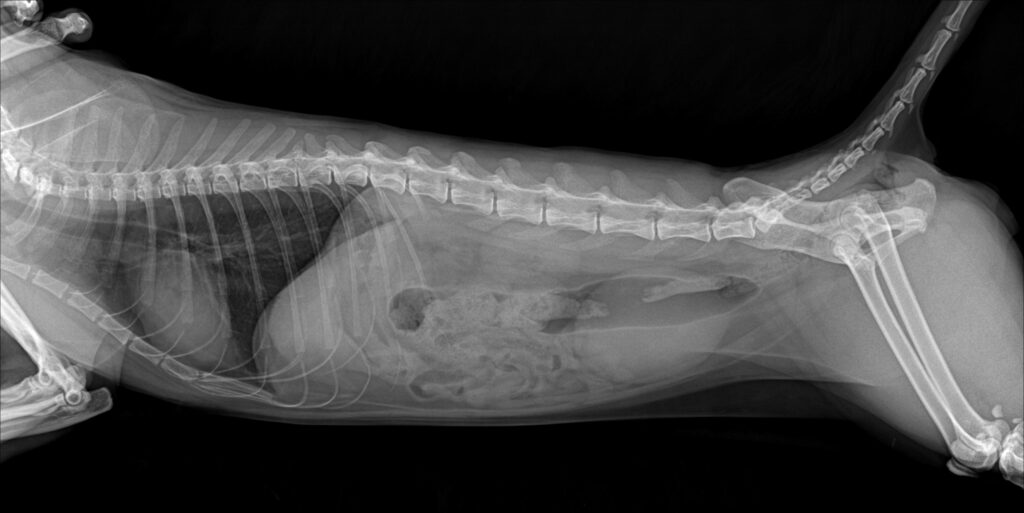

입원 5일차에 요도 카테터를 제거한 뒤 자발 배뇨 여부를 집중적으로 관찰하고, 방사선 검사를 통해 방광과 요도의 상태를 다시 한 번 확인했습니다. 원내 모니터링 결과 자발 배뇨가 원활하게 이루어지는 것이 확인되어 퇴원이 결정되었습니다.

환자 퇴원 직전 카테터 제거 후 엑스레이 사진 / 출처: 미래동물의료센터